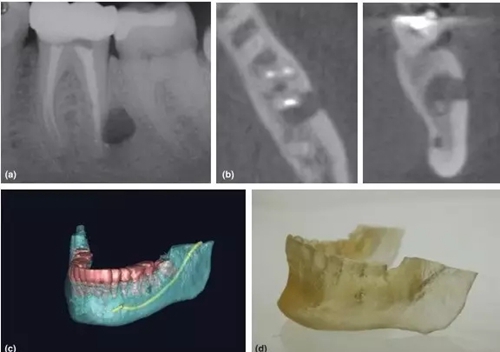

3,根尖周手術(shù)的術(shù)前評估

CBCT一直被倡導(dǎo)用于評估和設(shè)計根尖周手術(shù)方案 (Rigolone et al. 2003; Tsurumachi & Honda 2007; Kim & Kratchman 2006)。三維重建圖像讓臨床醫(yī)生能判斷根尖與鄰近重要解剖結(jié)構(gòu)的關(guān)系,如下頜神經(jīng)管、髁孔和上頜竇等。除外,還能精準測量骨損實際大小、與牙根的關(guān)系、皮質(zhì)骨板厚度、骨開窗情況和牙根的傾斜角度(Nakata et al. 2006)。

CBCT掃描還能配合3D打印技術(shù),把掃描的術(shù)區(qū)立體重建并打印出來,得出真實比例的研究模型,有助于術(shù)者對手術(shù)方案的設(shè)計和過程的演練(Scarfe et la. 2006)。